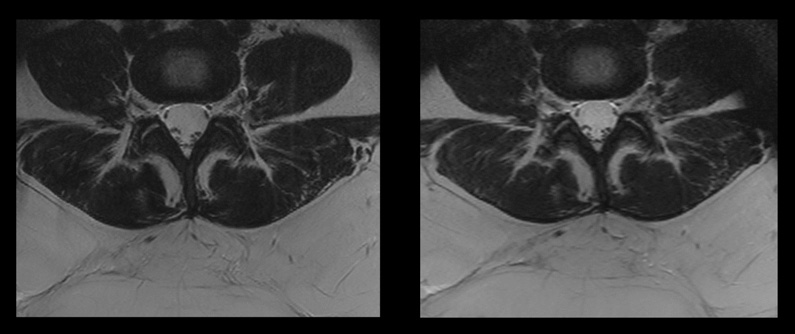

Comparison of two spine sequences with and without Compressed SENSE.

Image on the left: Conventional scan with SAR level of 2.5W/kg and a scan time of 7:33 min.

Image on the right: Compressed SENSE scan with SAR level of 1.9W/kg and a scan time of 3:21 min.